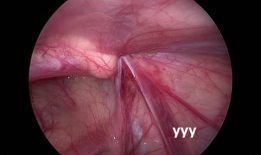

疝气手术视频,从术前准备到术后恢复

你有没有想过,当你在网上搜索“疝气手术视频”时,会出现什么样的画面呢?今天,就让我带你一起揭开这个神秘的面纱,看看那些让人既好奇...